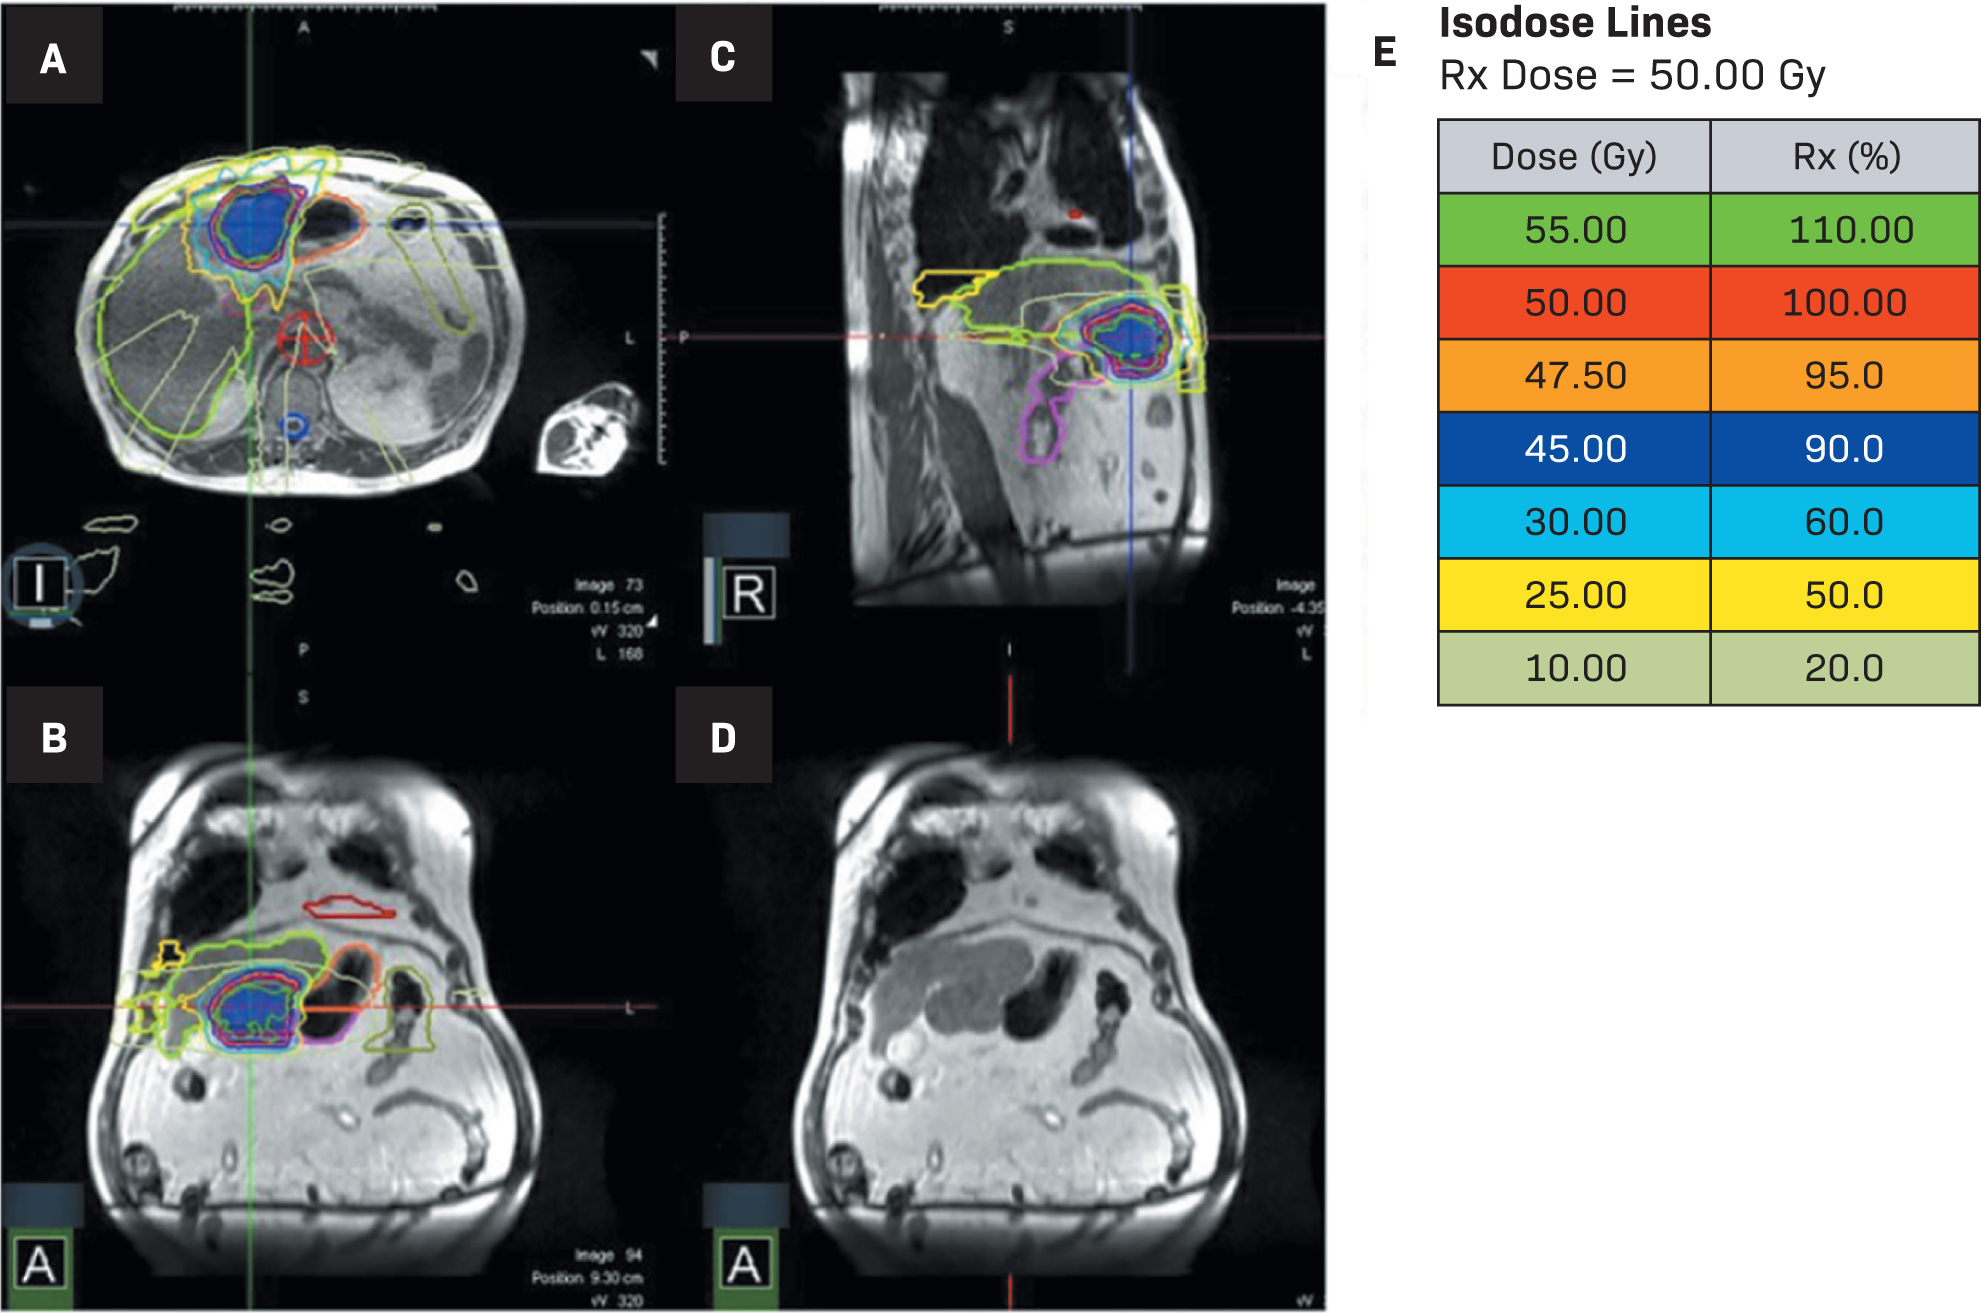

His most recent CT scan of the abdomen demonstrated a single site of active disease within segments 2 and 3 of the liver measuring up to 7 cm with an exophytic component causing abutment of the stomach (Figure 1), confirming the recommendation for MRI-guided SBRT. Given the proximity of the stomach to the tumor, endoscopic evaluation was performed within 3 months of the referral for radiation consideration and no invasion of the tumor into the stomach was observed. He underwent a planning CT and MRI simulation the following week. He was instructed to have nothing to eat for 3 hours prior to simulation and daily treatment. He received 50 Gy in 5 fractions with an adaptive workflow on the MRI linac (Figure 2). Overall time on the treatment table was roughly 1-1.5 hours, with no routine imaging post-treatment per institutional protocol. He tolerated treatment well, denying any acute side effects. All normal tissue constraints were met as per BR-0011 with the exception of the 5 cc constraint for duodenum, which we do not commonly use; however, all constraints were met based on Radiation Therapy Oncology Group (RTOG) 11122 (Table 1).

Diagnosis

The patient in this case completed adaptive MRgSBRT for 50 Gy in 5 fractions (Figure 2). Each of the 5 plans had luminal structures exceeding tolerance, requiring daily adaptation. Looking back at each predicted dose based on daily anatomic changes, the bowel/duodenum tolerance would have been exceeded on all days and the stomach tolerance would have been exceeded on days 2 and 4. To adapt the treatment, a 50-Gy optimization structure was created. The optimization structure was defined by the planning target volume (PTV) 50 minus planning organ at risk volume (PRV) of gastrointestinal (GI) structures (bowel, duodenum, and stomach plus 5 mm). With the adaptive workflow, we were able to meet all constraints daily and achieve reasonable coverage of the gross tumor volume (GTV) and PTV. At least 90% of the GTV received 50 Gy daily, and the area that was undercovered was the area abutting the stomach. The patient was treated with automatic beam gating and deep inspiratory breath hold for motion management.